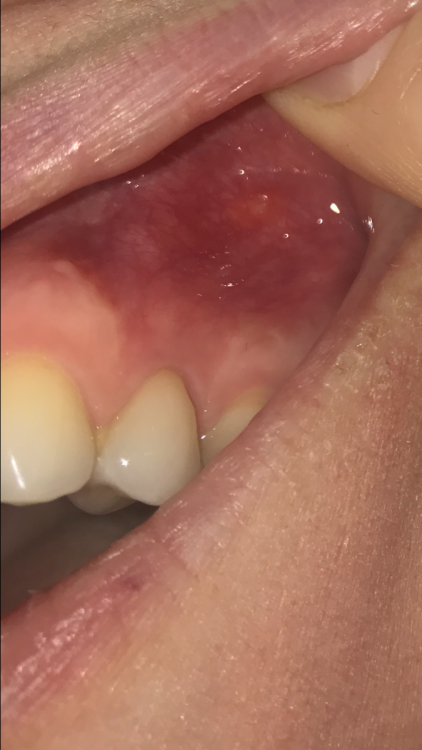

Vilka86 Опубликовано 1 января, 2022 Поделиться Опубликовано 1 января, 2022 Уважаемые доктора, огромная просьба помочь. лечила эндодонтически зуб 4 сверху слева. через год пришла к доктору, врач сказал зуб не вызывает опасений, приходить ещё через пол года. сегдня увидела шишку на десне у 5 зуба ..это свищ??? Прокомментируйте пожалуйста…. фото прилагаю. Плюс кт 2020 и 2021 года (декабрь). Буду очень благодарна если прокомментируете также. но хотя бы понять что за шишечка. Спасибо https://disk.yandex.ru/d/vHNLxcTcbEPiRA Ссылка на комментарий

red_butler Опубликовано 5 января, 2022 Поделиться Опубликовано 5 января, 2022 по фото больше на стоматит похоже, выкладывайте срезы Кт Ссылка на комментарий